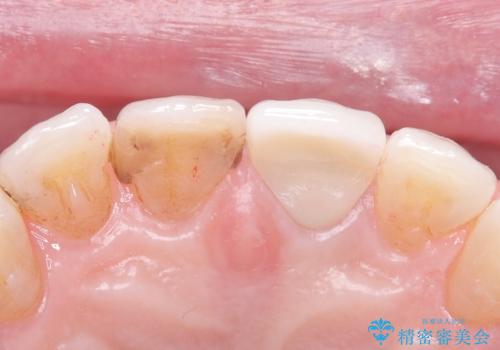

- 歯髄が死んで変色していた歯に対して、根管治療とオールセラミッククラウンでの修復を行いました。まず、根管治療で内部の感染を除去し、歯の強度を高めるためにファイバーコアを装着しました。その後、審美性と耐久性を考慮し、オールセラミッククラウンで覆うことで、自然な歯の色合いに近い美しい仕上がりを実現しました。

歯髄が死んだ歯は通常の健康な歯に比べて透過性が低く、特有の暗い色調を帯びる傾向にあります。変色は時間とともに進行し、薄い茶色や灰色、黄色がかった色合いになることが多いです。このような変色は、審美的な面で気になる場合が多く、オールセラミッククラウンなどでの修復が行われることも一般的です。